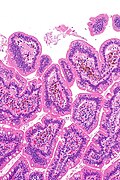

Template:Px Small bowel pseudomelanosis. H&E stain. | |

| LM | dark pigment in the lamina propria macrophages |

- Dark pigment in the lamina propria macrophages.

- Small bowel pseudomelanosis -- low mag.jpg

SBP - low mag. (WC/Nephron)

- Small bowel pseudomelanosis -- intermed mag.jpg

SBP - intermed. mag. (WC/Nephron)